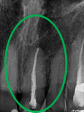

治療内容

レントゲンを撮り詳しく診てみると、歯根が破折して保存することができず、抜歯する必要があることがわかりました。抜歯後、オールセラミックブリッジで補綴(欠損した部分を人工物で補う)しました。ブリッジの支台になっている後方の歯は、根尖性歯周炎(根の先端で問題を起こしている)でしたので、根管治療をしています。

所感

抜歯後、欠損部分を補う方法には、1本だけの部分入れ歯、ブリッジ、インプラントの3つの方法があります。この患者さんは、ブリッジを選択されました。メタルフリーの治療を希望されましたので、土台をファイバーコアにし、オールセラミックのブリッジをかぶせました。患者さんは、お口の中の金属を徐々に減らしていきたいということです。体全体の健康のことを考えると正しいことです。

オールセラミック冠(失活歯)1本:¥104,500(税込)

オールセラミック冠(生活歯)1本:¥93,500(税込)

ポンティック1本:¥93,500(税込)

合計:¥291,500(税込)